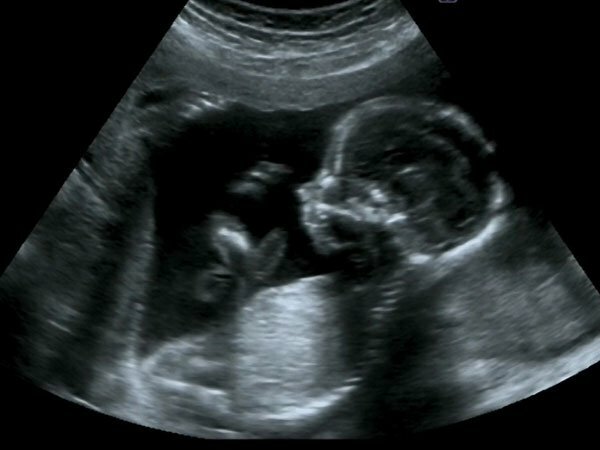

• Period: 63 to 280

Periodo de feto

Se trata de la tercera y última fase del periodo prenatal, que abarca desde la novena semana hasta el momento del parto